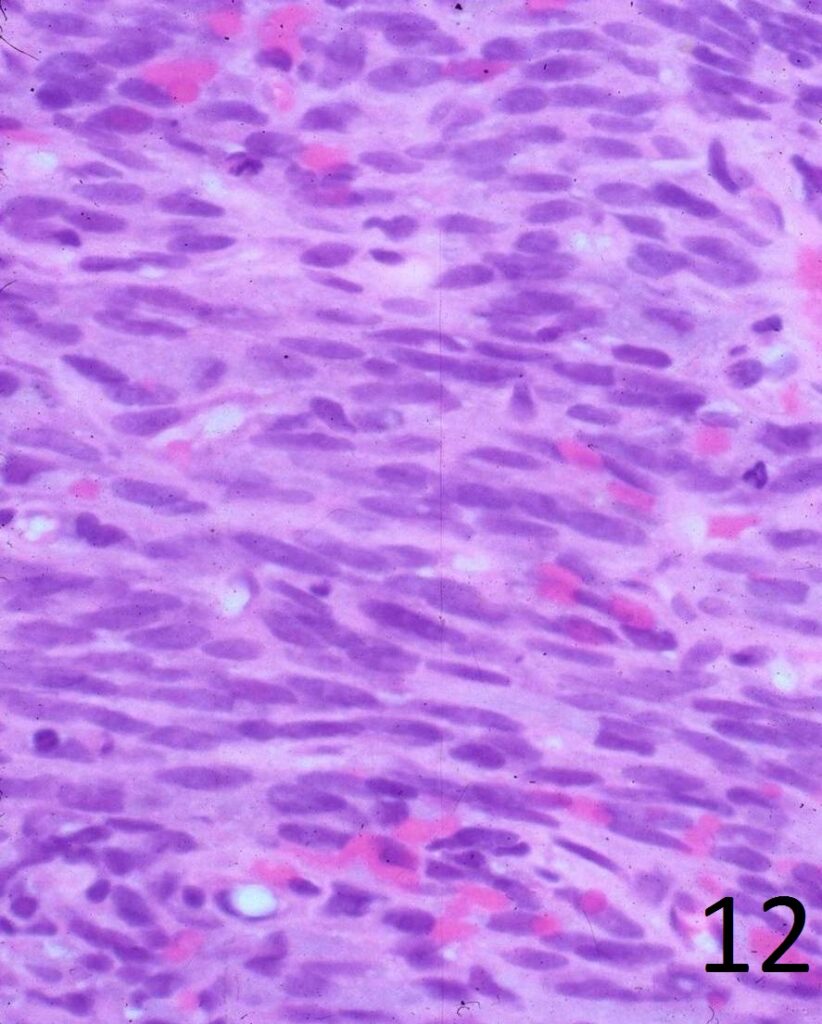

Microscopic

• Elongated, fairly uniform spindle cells with scant cytoplasm in a fibrous stroma

• Large nuclei with abnormal mitoses present; Higher grade tumors have more mitoses, necrosis and pleomorphism.

• Minimal pleomorphism with low grade tumors; More pleomorphism and mitoses with higher grade tumors

• Herringbone pattern (fascicles that intersect at right angles) (Fig. 11)

• Nuclei appear elongated with round ends (Fig. 12)